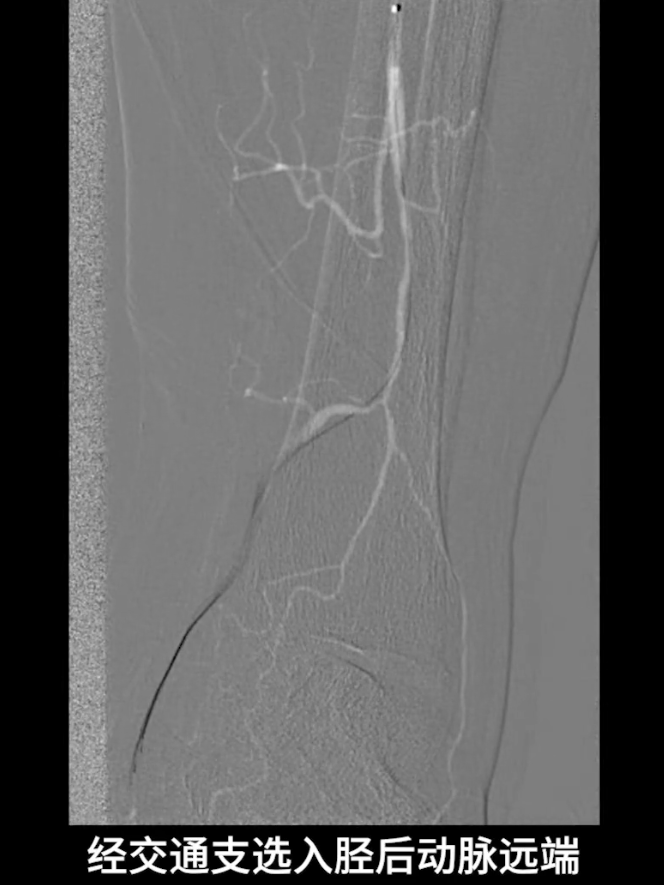

逆穿技术应用:改为逆穿胫后动脉远端,支撑导管配合V18导丝经交通支逆行进入腓动脉远端,逐步推送导丝导管通过胫腓干闭塞段,直至腘动脉近端真腔,与近端导管完成对接,建立膝下流出道操作轨道。

流出道扩张与优化:使用3.0×200mm PTA球囊对“胫腓干-腓动脉”全程进行扩张;

更换0.014系统导丝,经交通支选入胫后动脉远端,